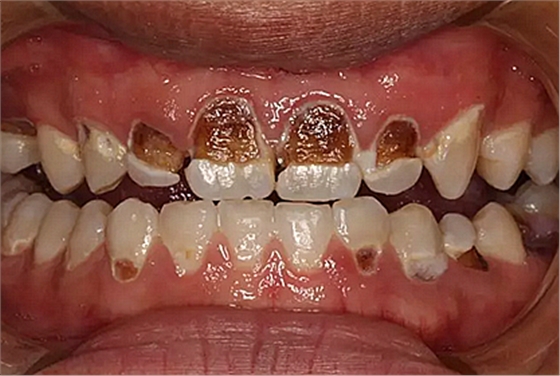

我們的主人今年才25歲,可卻從很小的時(shí)候就嗜好喝可樂等碳酸飲料,幾年下來,讓我們兄弟姐妹們整天浸在碳酸里受這蝕骨之痛,原本皎潔的外貌如今早己經(jīng)是腐蝕不堪、丑陋無(wú)比,更有甚者,一些兄弟姐妹們已經(jīng)病入膏肓,被病痛折磨奄奄一息。

下面是醫(yī)生眼中和ct下的我們

一身病痛啊

牙結(jié)石、牙齦炎癥、牙體殘缺、慢性牙髓炎、蛀牙......